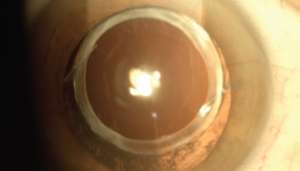

ICL, or Implantable Collamer Lens surgery, is a refractive procedure in which a permanent lens is implanted inside the eye, behind the iris and in front of the natural lens. Unlike LASIK, which reshapes the cornea using a laser, ICL adds a flexible lens inside the eye to help focus light correctly on the retina—correcting nearsightedness (myopia), astigmatism, and even extremely high prescriptions.